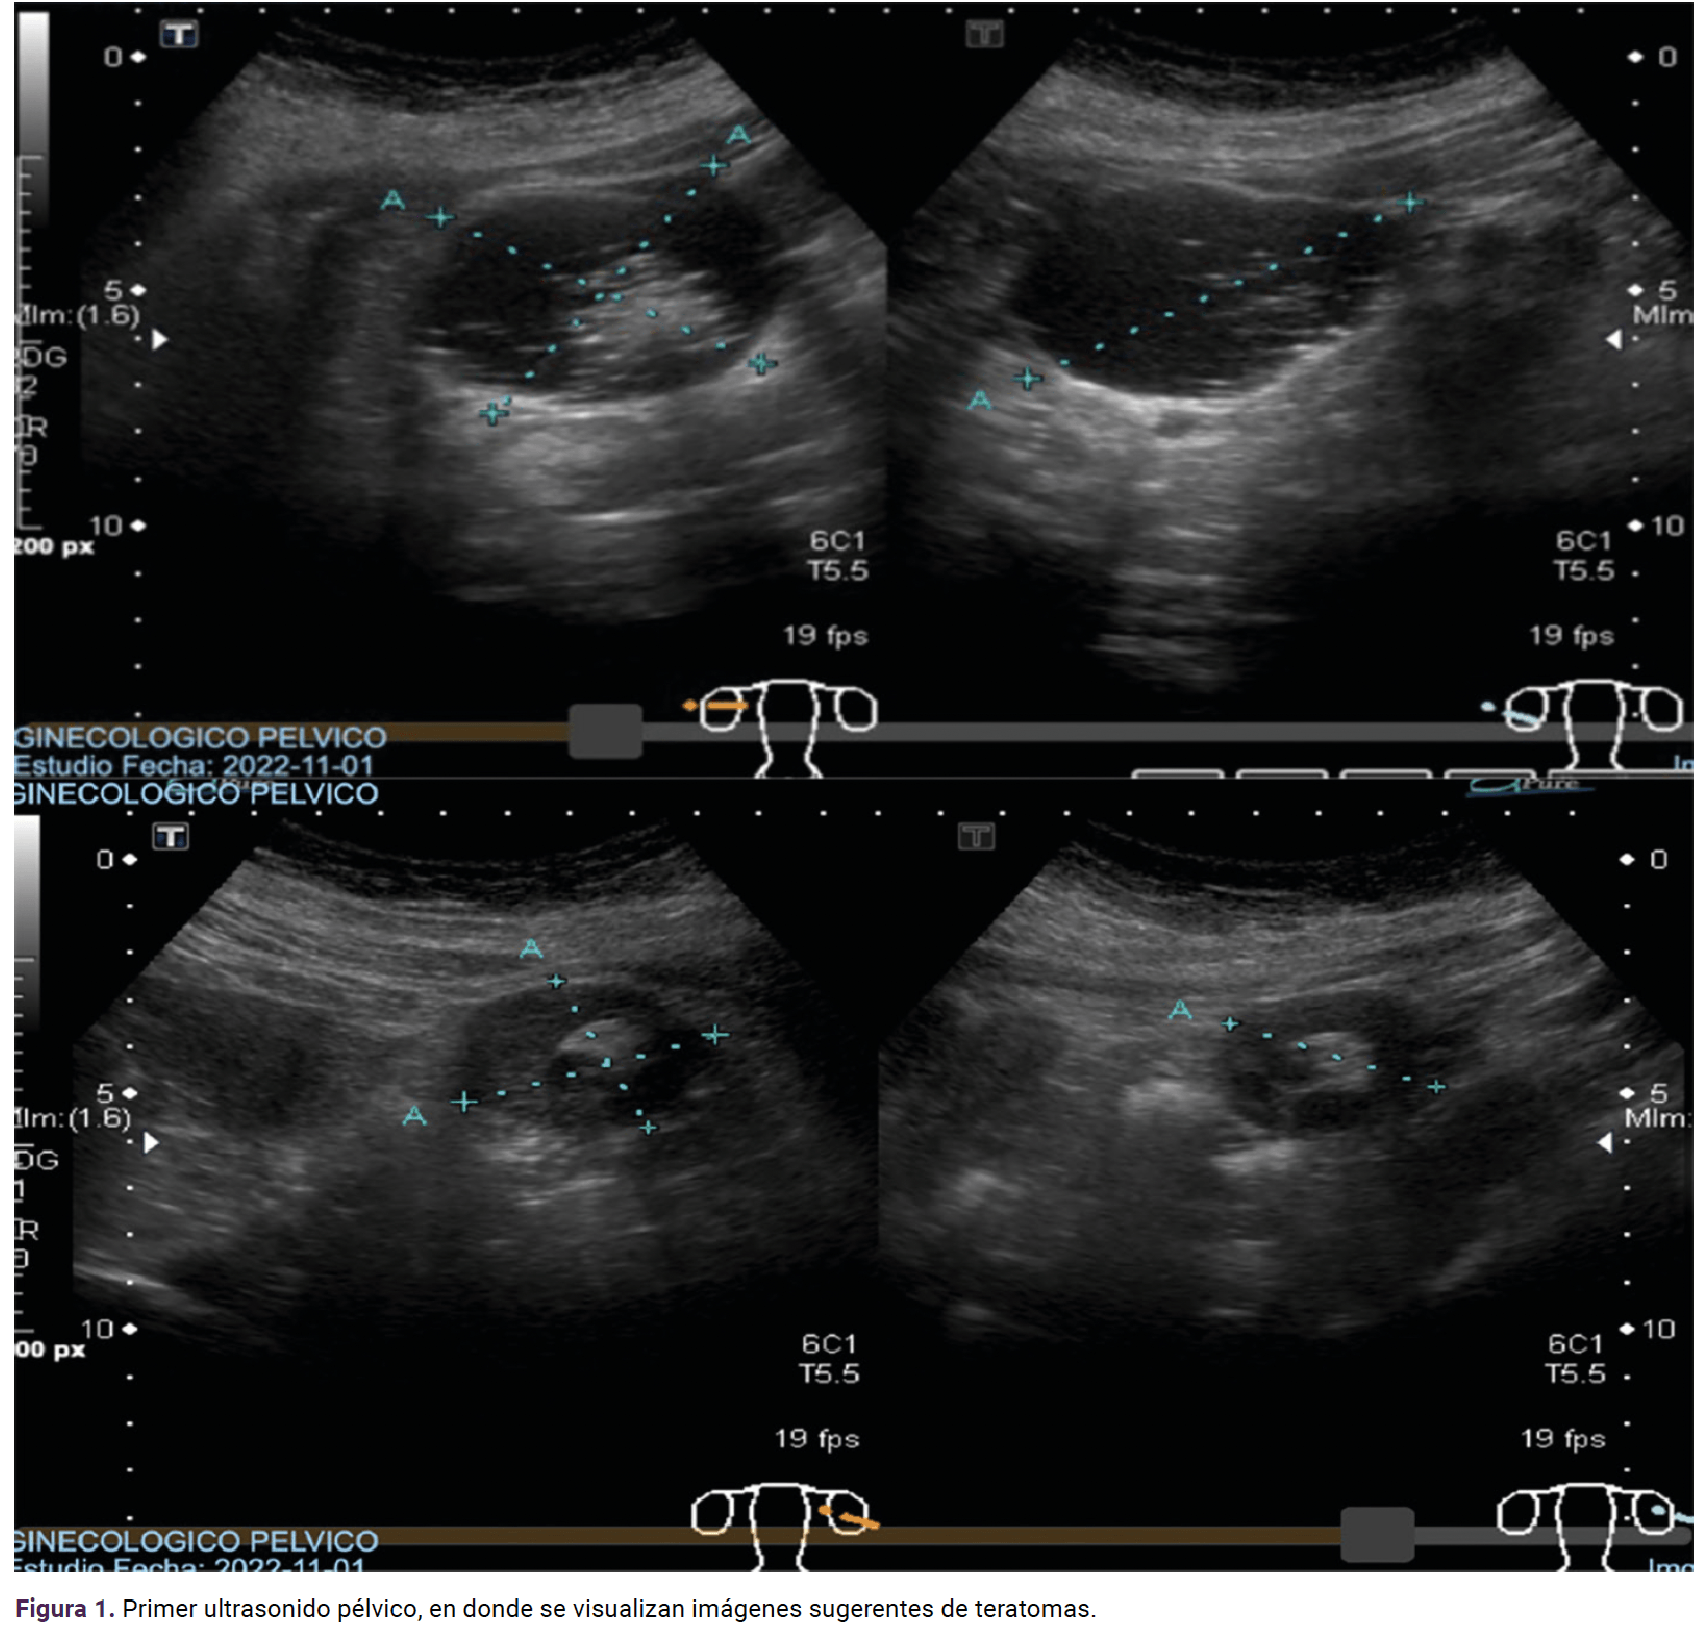

Los estudios de laboratorio reportaron: hemoglobina 13.8 g/dL; hematocrito 44.7%; plaquetas 191/mm3; glucosa 187 mg/dL; urea 14.9 mg/dL; creatinina 0.6 mg/dL, ácido úrico 6.6 mg/dL, CA 125 8.7 U/mL, ACE 1.1 ng/mL, AFP 1.06 ng/mL. El estudio de imagen describió: (Figura 1) útero en anteversoflexión, lateralizado a la derecha 81 x 34 x 51 mm, endometrio 7 mm, ovario derecho 63 x 60 x 71 mm, volumen de 141 cc, estroma completamente alterado con líquido predominante y dos nódulos murales altamente ecogénicos en su interior; el primero de 21 x 19 x 21 mm, el segundo izquierdo y medial de 12 x 12 x 12 mm sin flujo Doppler. El ovario izquierdo 42 x 34 x 25 mm, volumen 27 cc. En su interior se encontró líquido hipoecoico rodeado de un nódulo mural de 16 x 12 x 17 mm sin flujo Doppler. Las imágenes eran sugerentes de teratomas.

<strong>Figura 1</strong>

Figura 1